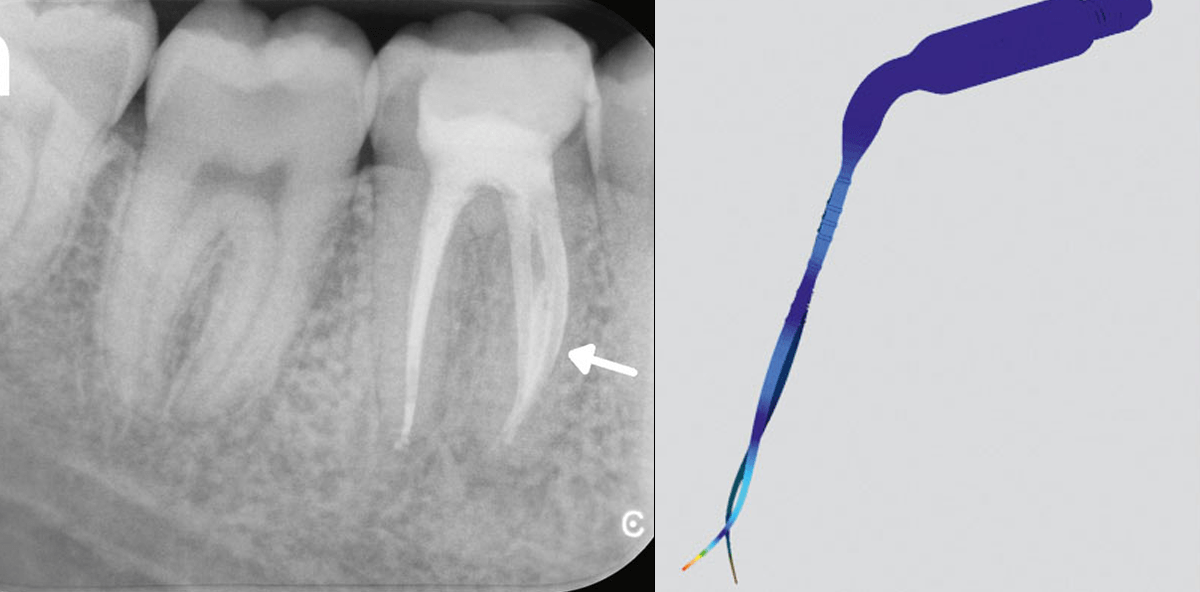

Eine Möglichkeit, die Effektivität von Spüllösungen signifikant zu erhöhen, ist deren Aktivierung mithilfe von Ultraschall.8 In der englischsprachigen Literatur wird hierbei häufig der Begriff „PUI“ verwendet. Übersetzt bedeutet er: Passive Ultraschallaktivierung. Ziel ist es, die Spüllösung nach der Aufbereitung im Kanal mit einem Instrument zu aktivieren, ohne die Kanalwand dabei zu berühren. Aus diesem Grund wurde der Begriff „passiv“ verwendet. Eine neuere Studie konnte jedoch zeigen, dass es sich hierbei bedingt durch die Auslenkung der aktivierten Instrumentenspitze keineswegs um eine passive Maßnahme handelt.9 Vor allem in stark gekrümmten Kanälen kommt es häufig zu Wandkontakten, wodurch die Gefahr einer Stufenbildung oder einer Instrumentenfraktur erhöht wird. Um die Effektivität der chemischen Desinfektion durch Aktivierung zu steigern und den Sicherheitsaspekt gleichzeitig nicht außer Acht zu lassen, hat der Flensburger Zahnarzt Dr. Winfried Zeppenfeld in langjährigen Versuchen die Idee für ein neues Instrument geboren, das von VDW (München) zu einem praxisreifen Produkt entwickelt wurde. EDDY® wird zur Schallaktivierung per Airscaler eingesetzt, wie er in den meisten Praxen vorhanden ist. Eine zusätzliche Investition in Form eines separaten Ultraschallgerätes entfällt somit. EDDY® ist eine Polyamidspitze, die durch ihre Geometrie und besonderen Materialeigenschaften im Bereich 5.000 bis 6.000 Hz die optimale Schwingungsfrequenz findet. Die schallaktivierte Spülung ermöglicht eine hochwirksame Reinigung des gesamten Wurzelkanalsystems. Gewebereste und Dentinspäne werden selbst in schwierig zugänglichen Bereichen, wie z.B. Isthmen in mesialen Wurzeln von Unterkiefermolaren oder Seitenkanälen (siehe Röntgenbilder), effektiv entfernt. Die Anwendung von EDDY® ist auch in gekrümmten Wurzelkanälen sicher und eine ungewollte Nachbearbeitung der Kanalanatomie ausgeschlossen, weil das verwendete Polyamid weicher ist als Dentin. Die Verwendung von EDDY® ist somit eine sichere und einfache Art, die Wahrscheinlichkeit einer erfolgreichen Wurzelkanalbehandlung deutlich zu erhöhen.